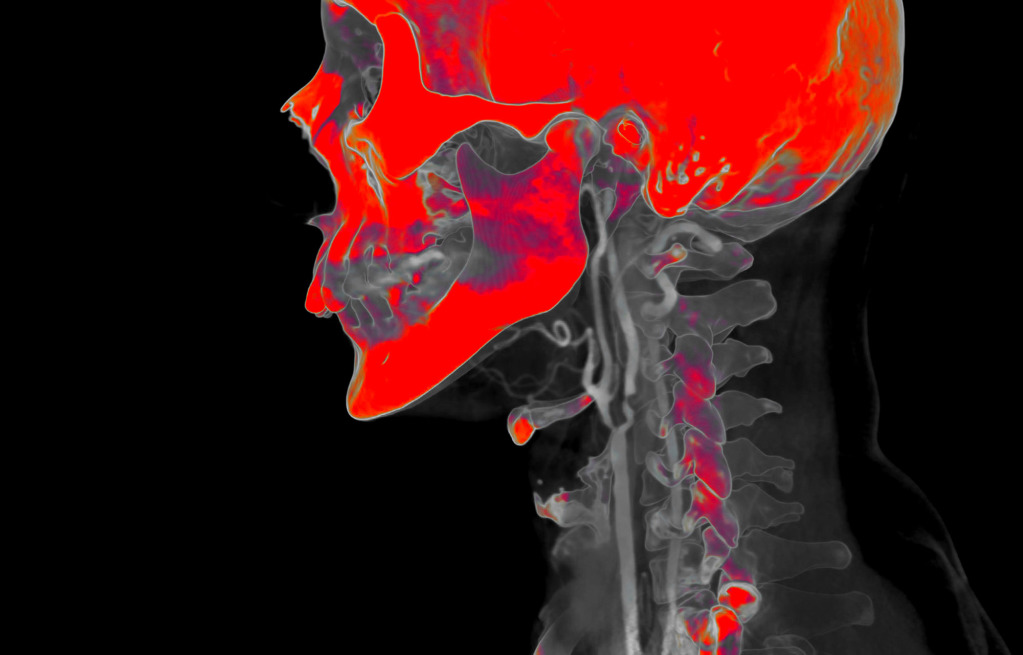

Most of the time, radiologists work with black and white images.

A multi-coloured, bright image is a way to shift the gaze and perceive things differently.

Also, I like to experiment with different photo filters and settings.

The program for processing radiological images (DICOM archives) allows you to create and look at a three-dimensional image from different angles.

If you change the location of the virtual lens, thereby changing the perspective, you can get such images.

How do you decide which colours to use on the images?

The colours choose themselves.

I simply create a table where the radiological density of the material can correspond to any colour.

After combining different shades, I only have to choose what I like the most.